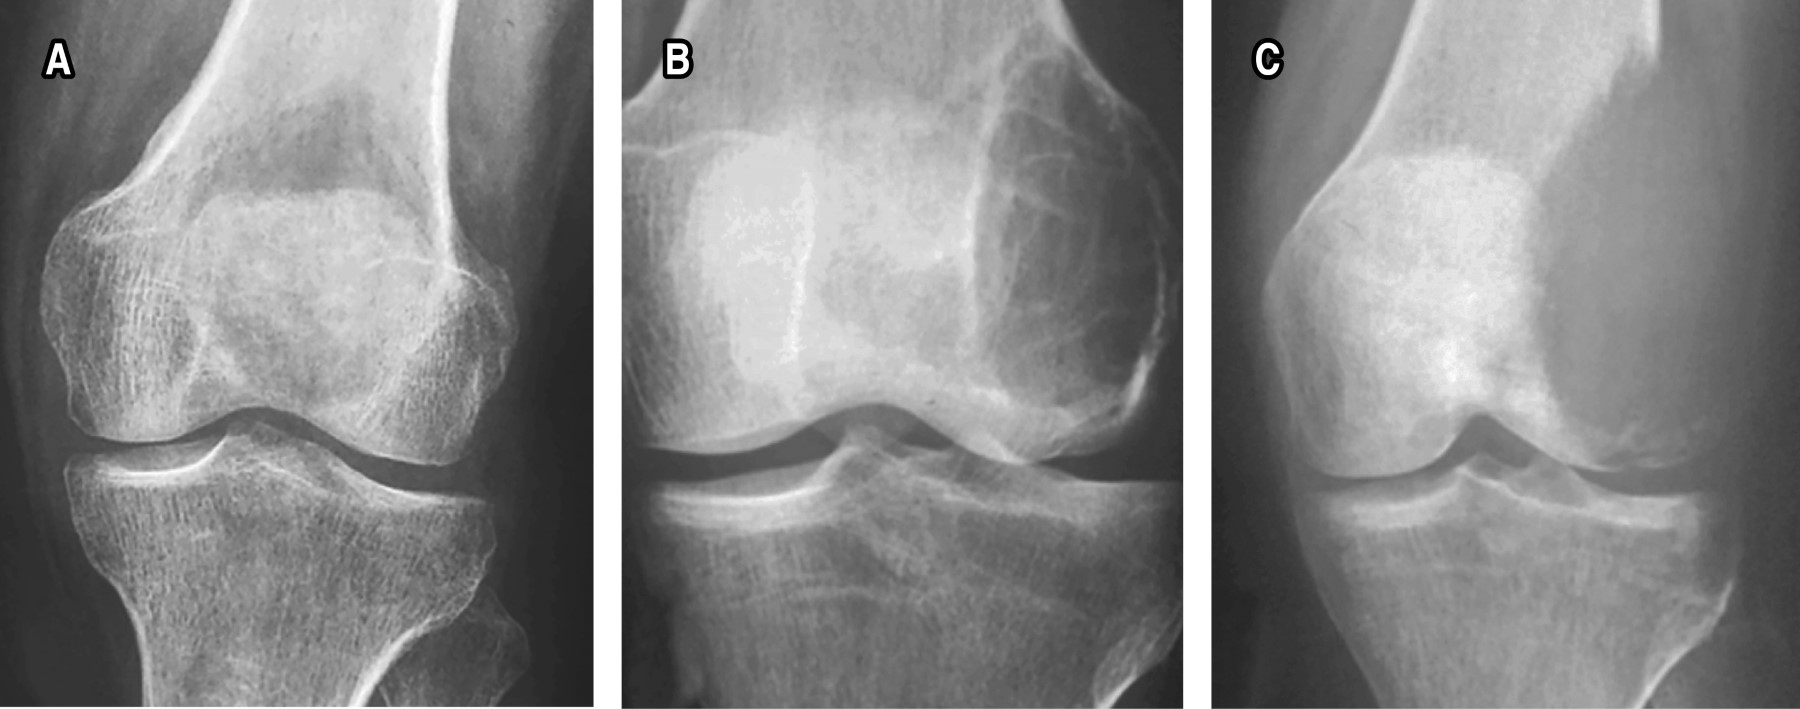

Giant cell bone tumor, treatment and diagnosis: literature review

The giant cell tumor (GCT) has a very versatile variety from the clinical presentation in gender and age group to its degree of malignancy, becoming fatal; radiographic classification is appropriate to determine the prognosis. Determining the histopathological diagnosis, which is currently the gold standard, is a pillar for treatment. Medical treatment from monoclonal antibodies for inoperable patients or degree of metastasis against the receptor for nuclear factor-κB ligand (RANKL) to reduce the size of the tumor and make it operable is the key in this. Other treatments such as embolization, laser photoablation, zolendronic acid, bisphosphonates or even adjuvants to surgical treatment such as liquid nitrogen and ethanol at the time of curettage are options for this pathology. The objective of this review is to determine the current epidemiology, classification, pathophysiology, clinical picture, diagnosis, medical and surgical treatment in order to have an overview and guide in the follow-up of this pathology.

Figure 1